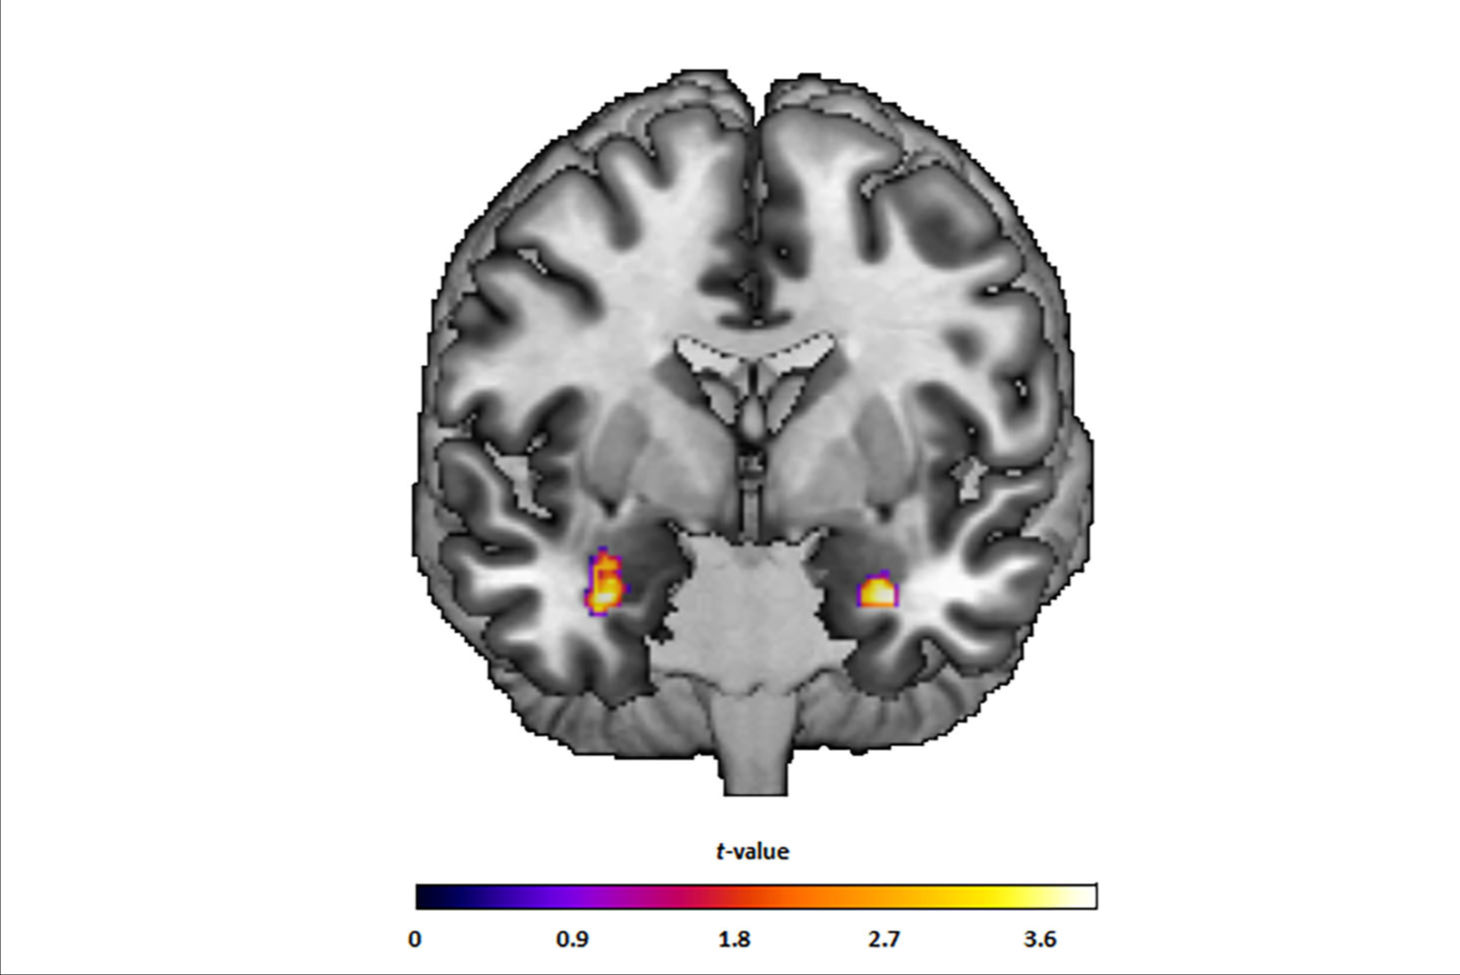

The session, "New Alzheimer's Therapies - Radiological Accompanying Phenomena in Focus," will provide a practical overview of typical MRI findings, image morphological progression, and risk factors for amyloid-related imaging abnormalities (ARIAs). It will use numerous case studies and participants will receive tips on standardized diagnostics, differential diagnosis, and reliable assessment of the progression.